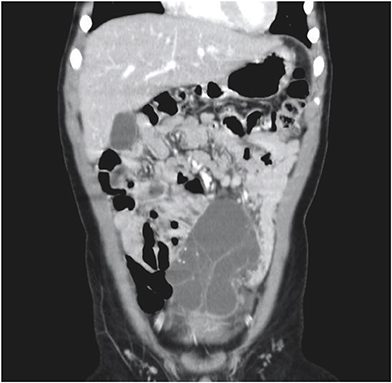

All patients underwent abdominal ultrasonography and computed tomography (CT) scans. In patient No. 7, these modalities showed a cystic mass, 9 cm in size, with multiple septa in the lower abdomen (Figs. 1, 2). An abdominal CT scan of patient No. 9 showed a huge multiloculated cystic mass with a septum; this mass occupied nearly the entire abdominal cavity and caused the displacement of the bowel to the left posterior abdomen.

Fig. 1

Abdominal ultrasonography of patient No. 7, showing a hypoechoic cystic mass with an ovoid wall, separated by intracystic septation in the lower abdomen.

Abdominal lymphatic malformations are very difficult to diagnose before surgery, with most patients diagnosed by postoperative biopsy. No specific radiologic findings can confirm abdominal lymphatic malformations before surgery. Abdominal ultrasonography or CT is necessary for accurate diagnosis before surgery, with these modalities providing information on lesion location and size and association with adjacent lesions. On abdominal ultrasonography, these lesions appear as hypoechoic cystic masses with a round wall separated by echogenic septa in the cystic space [37]. Abdominal CT scans provide more information before surgery about lesion location, size, and association with adjacent lesions. Typically, shading of the contents is homogeneous, with CT scans showing a single or polycystic mass with thin walls, as well as showing the relationship of the lesion with adjacent organs and blood vessels [319]. Abdominal magnetic resonance imaging (MRI) does not provide more information than ultrasonography or CT about lesion location, but it may be helpful in diagnosing complications such as hemorrhage. CT scanning is useful diagnostically, but ultrasonography and MRI may be better for children because of low radiation exposure. The differential diagnosis of abdominal lymphatic malformations includes other cystic abdominal masses, such as choledochal cysts, urachal cysts, ovarian cysts, renal cysts, intestinal duplications, abdominal lymphoma, simple mesenteric cysts, and pancreatic pseudocysts [82021].